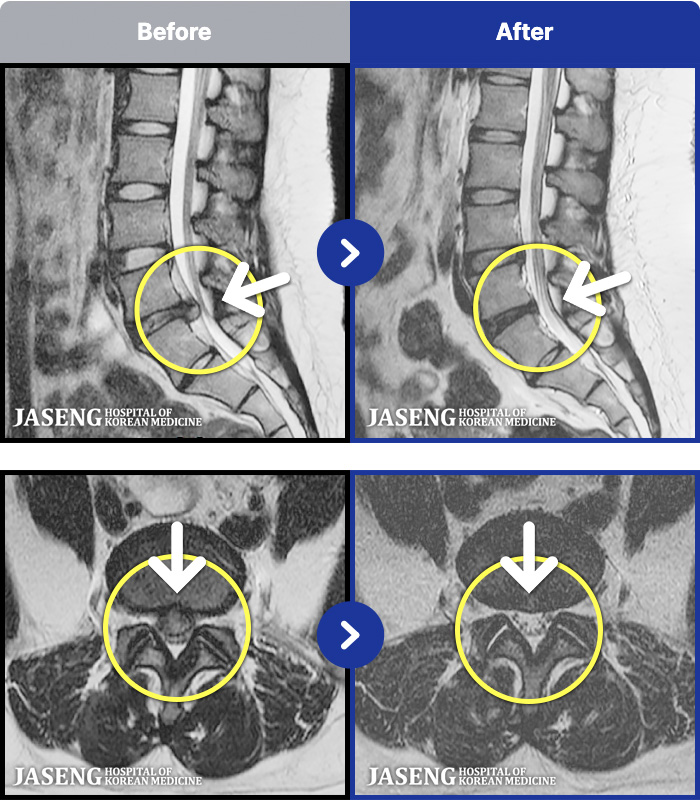

MRI ġ

1,240 MRI ũ ʸ Ȯϼ.